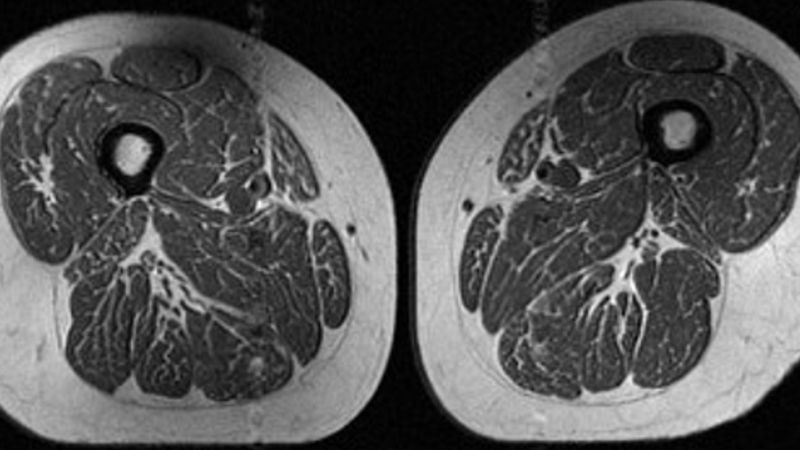

The phrase “processed foods are making our thighs look like marbled steak” is provocative, isn’t it? But it holds a potent truth. We’re not talking about literally seeing fat streaks like a Wagyu cut. Instead, it’s a powerful metaphor for what happens to our body tissue – specifically, how fat gets stored and distributed, and how the quality of our muscle and connective tissue can change. Imagine the subtle, pervasive infiltration of unhealthy fat cells, not just beneath the skin, but interwoven within our muscle fibers, diminishing tone and firmness. This isn’t just aesthetic; it’s a profound shift in our body’s fundamental composition.

Think about it: a diet rich in these items isn’t just adding calories; it’s actively remodeling your body from the inside out. Your body isn’t just getting fatter; its very structure and texture are changing, becoming less dense, less toned, and more prone to the kind of soft, yielding quality we associate with marbled meat.